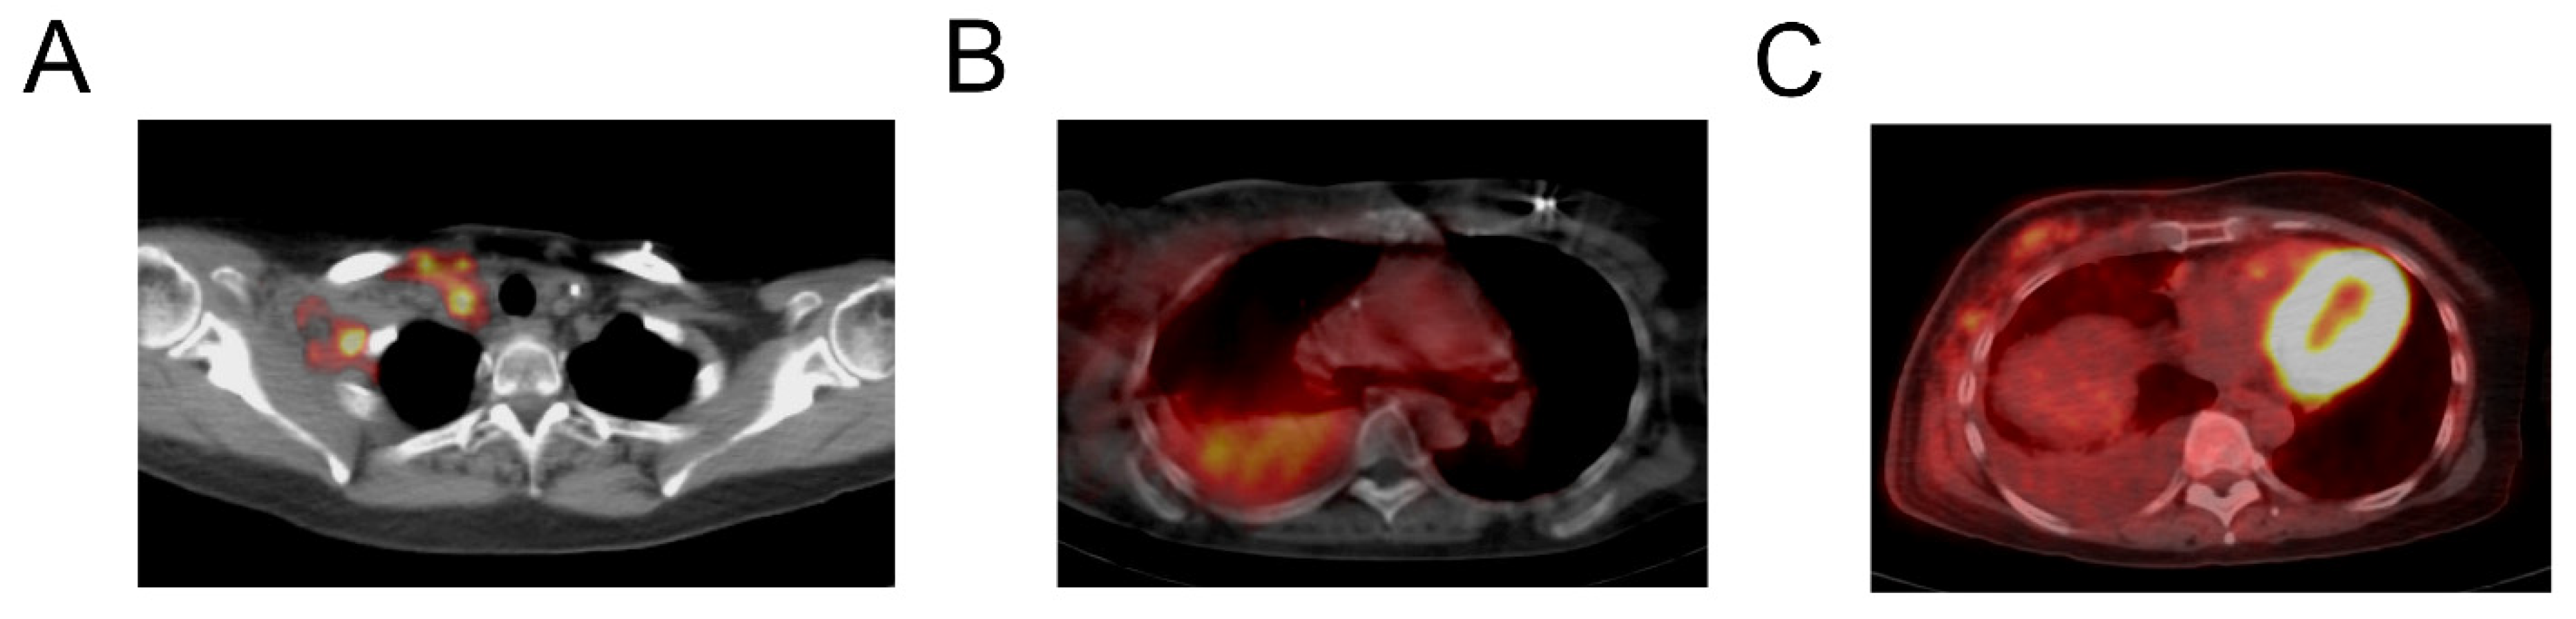

Uptake of [124I]I-NM404was observed within metastatic lymph nodes in a variety of primary tumors (Figure 5). CT correlation was useful for localization of [124I]I-NM404activity within nodal disease. Examples of nodal uptake were seen with [124I]I-NM404 PET imaging. Beyond brain, lung, lymph node, and bone metastases, several other sites of active metastatic disease were demonstrated with [124I]I-NM404 in this heterogeneous patient cohort. Failed detection of hepatic metastatic disease with [124I]I-NM404 in one case appeared to be related to a lack of delayed imaging, although the low injected dose (185 MBq) may have also contributed. Increased uptake was also seen within body wall soft tissue involvement (Figure 5A). Increased [124I]I-NM404 activity was observed in two patients with cytology-proven malignant pleural effusions, one with triple-negative breast cancer and the other with bronchogenic carcinoma. Neither of these malignant pleural collections showed increased [18F]FDG uptake, and increased [124I]I-NM404 uptake was not observed in cases of benign pleural effusions, suggesting utility for [124I]I-NM404 PET with malignant pleural involvement.

Figure 5. A 53-year-old woman with metastatic triple-negative breast cancer imaged with both [124I]I -CLR1404 and [131I]I-CLR1404. Fused PET/CT image (A) obtained 6 days after 124I-CLR1404 administration shows abnormal uptake within the right axillary and cervical region, corresponding to metastatic involvement of the body wall and lymph nodes. Fused SPECT/CT image (B) obtained 21 days after injection of [131I]I-CLR1404 shows increased activity within a moderate-sized right pleural effusion, which was proven malignant by cytology after thoracentesis. Increased pleural uptake was also seen on [124I]I-CLR1404 PET (not shown) but not on [18F]FDG PET (C). Note also prominent myocardial uptake with FDG, which is generally not seen with CLR1404.